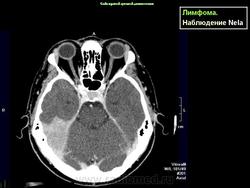

Диагноз подозревается на основе изображений КТ и МРТ.

Лимфома задней черепной ямки

TC Craneoencefálica (Linfoma cerebral)

Linfoma Cerebral